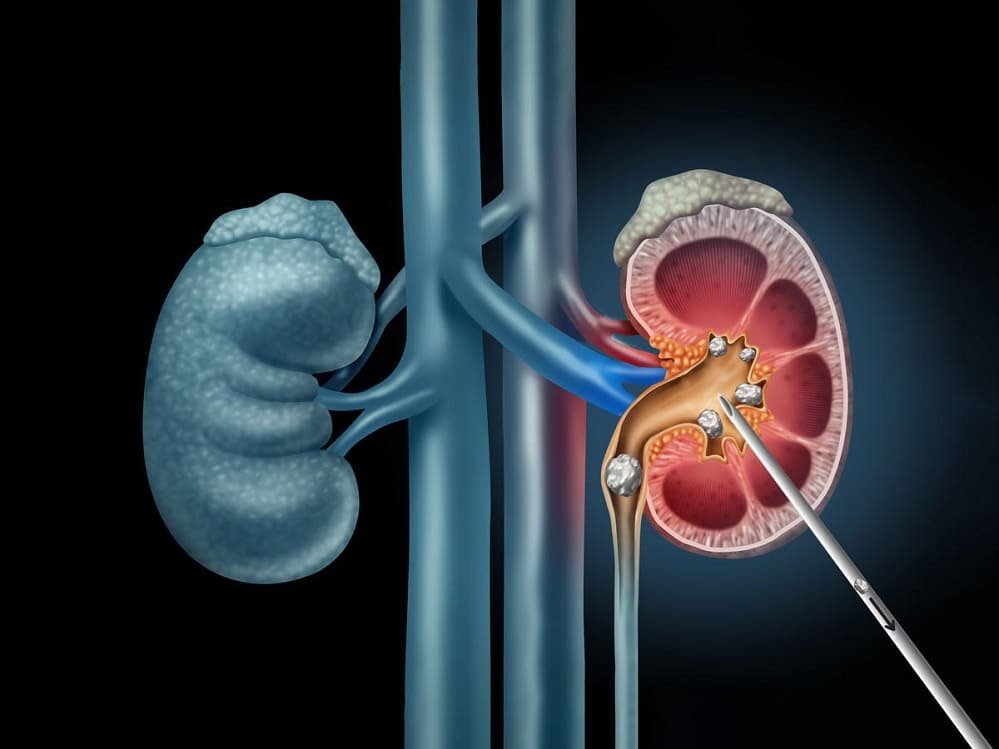

Percutaneous Nephrolithotomy (PCNL) is a minimally invasive surgical procedure designed to remove large or complex kidney stones from the renal pelvis and calyces. First introduced in the late 1970s, PCNL has revolutionized the management of nephrolithiasis, offering a more effective alternative to open surgery for stones that are too big for less invasive methods like extracorporeal shock wave lithotripsy (ESWL) or ureteroscopy. The term “percutaneous” refers to accessing the kidney through the skin, bypassing traditional abdominal incisions. This technique involves creating a tract from the skin to the kidney under imaging guidance, allowing direct visualization and fragmentation of stones using specialized instruments. PCNL is particularly valuable for staghorn calculi—large, branching stones that fill the renal pelvis—or stones greater than 2 cm in diameter, where complete clearance is essential to prevent recurrent infections, obstruction, or kidney damage.

Puncture and Tract Dilation: Using intravenous contrast or retrograde pyelography, the collecting system is opacified. A urologist, guided by fluoroscopy, inserts an 18-gauge needle through the skin into a posterior calyx—ideally the lower pole for better drainage. Urine is aspirated to confirm entry, and a guidewire is advanced into the renal pelvis and ureter. The tract is dilated sequentially using balloons or Amplatz dilators up to 24-30 French (Fr) gauge, creating a channel about 8-10 mm wide. A peel-away sheath is placed to maintain access.

Nephroscopy and Stone Fragmentation: A rigid nephroscope (24-32 Fr) is inserted through the sheath, allowing direct visualization of the renal interior via fiberoptic lenses. Stones are engaged with graspers for intact removal if small, or fragmented using ultrasonic, pneumatic (ballistic), or laser lithotripters. For staghorns, multiple accesses might be needed, though single-tract “all-seeing” techniques minimize this. Irrigation fluid (normal saline) flushes fragments, and a nephrostogram checks for residual stones.

Placement of Tube and Closure: Once cleared, a nephrostomy tube (22 Fr) is left in the tract for drainage, connected to a bag. In select cases, “tubeless” PCNL omits the tube, using a ureteral stent instead for faster recovery. The skin puncture is closed with sutures or glue. The procedure lasts 1-3 hours, depending on stone complexity.